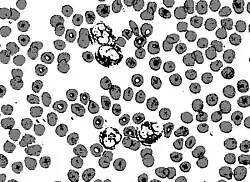

Circular thresholding is an algorithm for automatic image threshold selection in image processing. Most threshold selection algorithms assume that the values (e.g. intensities) lie on a linear scale. However, some quantities such as hue and orientation are a circular quantity, and therefore require circular thresholding algorithms. The example shows that the standard linear version of Otsu's method when applied to the hue channel of an image of blood cells fails to correctly segment the large white blood cells (leukocytes). In contrast the white blood cells are correctly segmented by the circular version of Otsu's method.